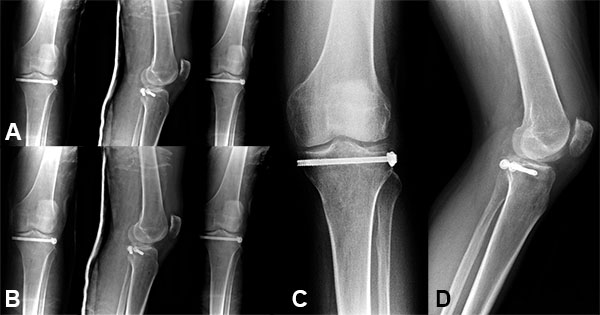

Figura 3: Control post quirúrgico al año.

Nuestro seguimiento osciló entre 6 meses y 24 meses, sin que observáramos cambios radiográficos.

Radiológicamente obtuvimos 7 resultados excelentes y 1 bueno. En todos los casos no observamos desplazamientos secundarios de la fractura y obtuvimos la consolidación definitiva.

Utilizamos como método de fijación la colocación de dos tornillos de esponjosa canulados de 6,5 mm con arandela colocados en forma percutánea bajo control radioscópico. De esa manera evitamos la realización de grandes abordajes quirúrgicos y sus consecuencias: rigidez, dolor e infecciones profundas.

Los resultados radiológicos obtenidos nos sugieren que la fijación con dos tornillos percutáneos subcondrales es suficiente para mantener la estabilidad hasta lograr la consolidación, y evita la disección mayor de los tejidos blandos requerida para la colocación de placas y tornillos.